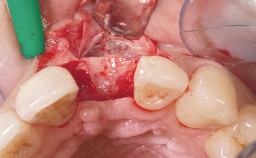

Immediate Flapless Placement of an Implant in a Maxillary Left Central Incisor Site

A 42-year-old female patient was referred to our clinic at the School of Dentistry of the University of São Paulo in November 2004, presenting a deficient restoration in the upper left central incisor. The clinical examination revealed no gingival retraction or any signs of gingival inflammation and, therefore, previous periodontal treatment was not considered. The patient presented a high lip line at full smile and a thin tissue biotype. This combination characterized a high-risk situation from an anatomic point of view, which required careful preoperative planning and cautious surgical execution.

Soft Tissue Grafting None

Soft Tissue Anatomy Intact Defective

Bone Volume Horizontally and vertically sufficient Horizontally deficient Deficient vertically or deficient vertically AND horizontally